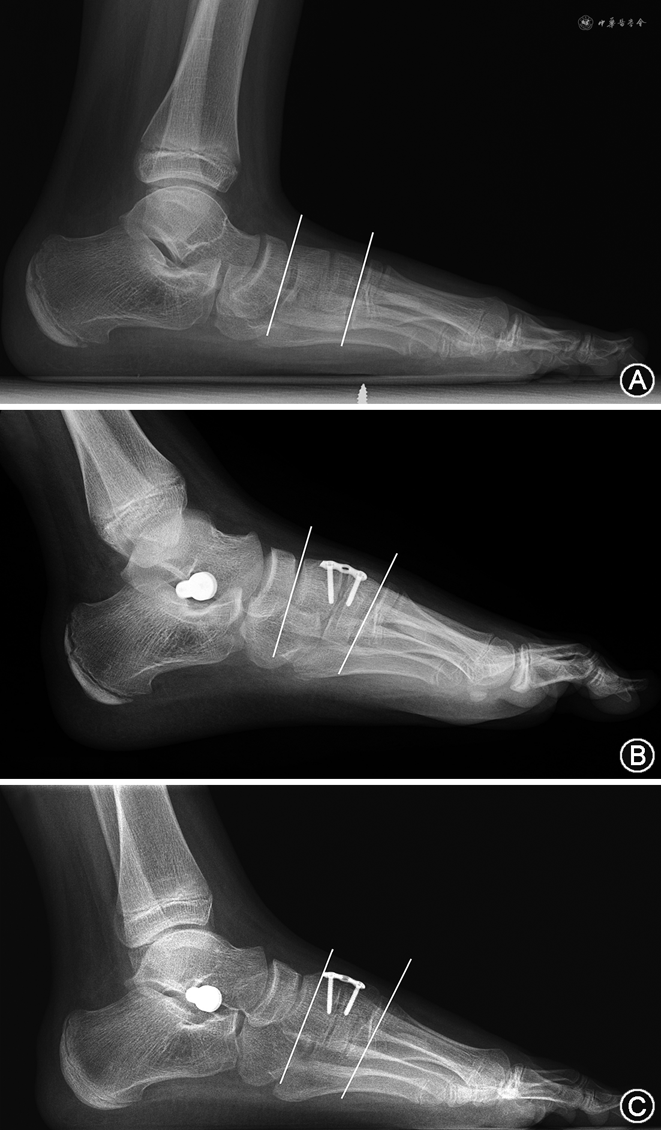

患儿男,12岁,主因左足副舟骨区疼痛1年入院。病史中曾行足垫、减少体育活动、外用药等保守治疗半年,疼痛无明显缓解,日常活动行走500 m以上疼痛,需要休息。体育活动受限。术前查体:可及副舟骨区压痛,胫后肌腱肌力因疼痛减弱,为4级。后足外翻,腓肠肌挛缩。辅助检查:X线可见跟骨外翻,距舟关节无明显脱位。术前测量角度见图3。术前AOAFS评分32分,VAS评分8分,Maryland评分40分。术后1年随访时AOFAS评分89分,VAS评分1分,Maryland评分92分。

影像学评估足X线负重正位距骨第1跖骨角(talo-1st metatarsal angle,T1MT)、距舟覆盖角(talo-navicular coverage angle,TNCA)、距骨跟骨角(talocalcaneal angle,TCA)、足负重侧位距骨第1跖骨角(Meary角)、跟骨倾斜角(Pitch角)、距骨跟骨角(Kite角)、内侧楔骨关节面夹角(cuneiform articular angle,CAA)及后足力线角(hindfoot alignment angle,HAA)[12]。为了单独评价Cotton截骨的矫形能力,根据Castaneda等[13]的报道,采用CAA用来评价Cotton截骨术矫正前足内翻的能力。CAA测量方法如图2所示:即内侧楔骨近端背侧与跖侧关节面连线与远端关节面上下角的连线,形成夹角。行背侧撑开植骨后,夹角增大。

1. 术前术后角度测量对比:末次随访时两组TCA均较术前差异无统计学意义(均P>0.05);末次随访时,两组其余各角度均较术前明显改善,差异均有统计学意义(均P<0.05)。髂骨组CAA角中位数由术前的1.6°增至末次随访的7.7°,副舟骨组由2.6°增至6.6°,差异均有统计学意义(均P<0.05)(表2)。

3. 两组间末次随访角度与功能评分对比:两组患者随访结果进行组间对比,发现术后两组CAA均值对比差异有统计学意义(Z=-2.14,P=0.031),髂骨组和副舟骨组分别为7.7°和6.6°。其他角度指标差异均无统计学意义(均P>0.05)。

进一步分析两组植骨纠正量,采用病例术后末次随访的CAA角度减去术前CAA角度,得到∆CAA。经统计分析,此增量值∆CAA具有正态性。髂骨组∆CAA为6.0°±2.6°,副舟骨组为4.3°±1.3°,两组间差异有统计学意义(t=2.52,P=0.017)。末次随访时,两组间各功能评分比较差异均无统计学意义(均P>0.05)。

Castaneda等[13]提出CAA用来评价Cotton截骨术矫正前足内翻的能力,同时可评价截骨量丢失。结果发现CAA角由术前1.0°增加至术后8.4°,且末次随访时CAA角能保持在7.5°左右。在此后的几项研究中同样证实了CAA角可用来单独评价Cotton截骨的矫形能力[25, 26, 27, 28]。本研究中CAA测量指标,髂骨组由术前中位数1.6°增加至术后7.7°,副舟骨组由术前中位数2.6°增至术后6.6°。虽然副舟骨组术后CAA角已有显著改善,但与髂骨组相比仍有一定差距。此差异来源于副舟骨尺寸有限而髂骨取骨量较充足。因此在副舟骨植骨手术中,应当注意骨量的宽度,以更多改善CAA角度。然而从末次随访功能评价来看,两组间不存在差异。影像学X线测量的其他角度也不存在差异。虽然CAA角度可以很精确地反映楔骨撑开的效果,但从足整体结构看,两组间差异不足以削弱Cotton截骨术的矫正效果。